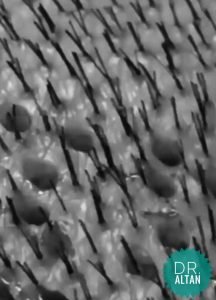

W dniu transplantacji włosów, są one skracane całkowicie w celu łatwiejszego pobrania mieszków włosów.

Podstawową przyczyną łysienia androgenowego jest nadwrażliwość organizmu na DHT, czyli pochodną testosteronu. DHT w sposób pośredni wpływa na miniaturyzację mieszków włosowych, co skutkuje mniejszą ilością włosów w skupisku mieszka włosowego, finalnie ich zanik.

W pierwszym etapie łysienia androgenowego dochodzi do cofnięcia linii włosów w okolicy skroni, czyli powstania tzw. zakoli. To właśnie w tym momencie wiele osób decyduje się na podjęcie leczenia lub przeszczep włosów.